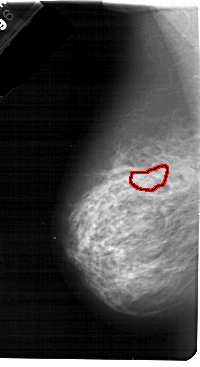

A_1766_1.LEFT_MLO

FILE: A_1766_1.LEFT_MLO.OVERLAY

TOTAL_ABNORMALITIES 1

ABNORMALITY 1

LESION_TYPE CALCIFICATION TYPE PLEOMORPHIC DISTRIBUTION CLUSTERED

ASSESSMENT 4

SUBTLETY 1

PATHOLOGY MALIGNANT

TOTAL_OUTLINES 1

BOUNDARY